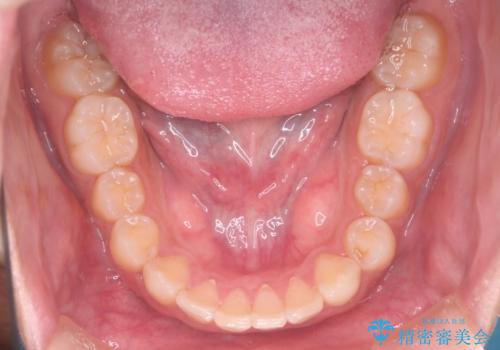

インビザラインにて治療を行うことで、前歯のがたつきが改善されました。

左上1番目の前歯はセラミックをご希望されたので、セラミックにて被せ物の治療を行いました。

とても綺麗な前歯になりました。